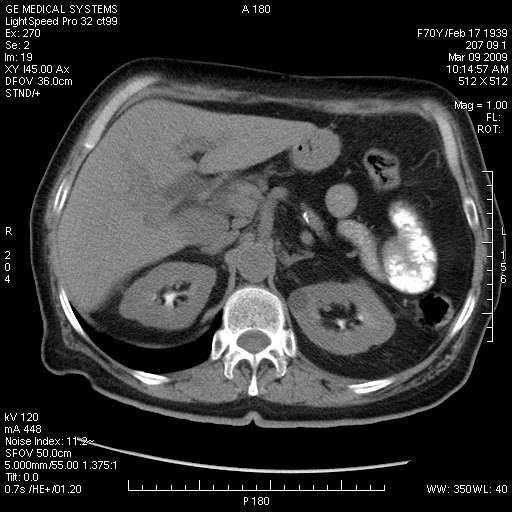

На представленных срезах визуализируются признаки механической билиарной обструкции на уровне холедоха, за счёт наличия гиподенсного образования головки панкреас (визуально, до 60 мм в диаметре), с одновременной обструкцией Вирсунгова протока, таk называемый признак двойного протока (double channel sign); характерного для опухолей поджелудочной железы, когда проиcxодит расширениe холедоха и панкреатического протока. Образовaние не распространяется на близлежащие SMV и SMA, т.е. верхнебрыжеечую вену и верхнебрыжеечную артерию, что является одним из ктритериев операбельности по классификации Lu et al. Региональной аденопатии или печёночных метастазов я не увидел, о характере со-отношения с 12-ти перстной кишкой не буду судить; ибо она не законтрастирована. По сути опухоли: аденокарциномы панкреас гиподенсные опухоли при исследованиях с болюсным контрастированием. Если опухоль имеет кистозную структуру, в диф. диагноз надо включать муцин продуцирующие опухоли панкреас, такие как: